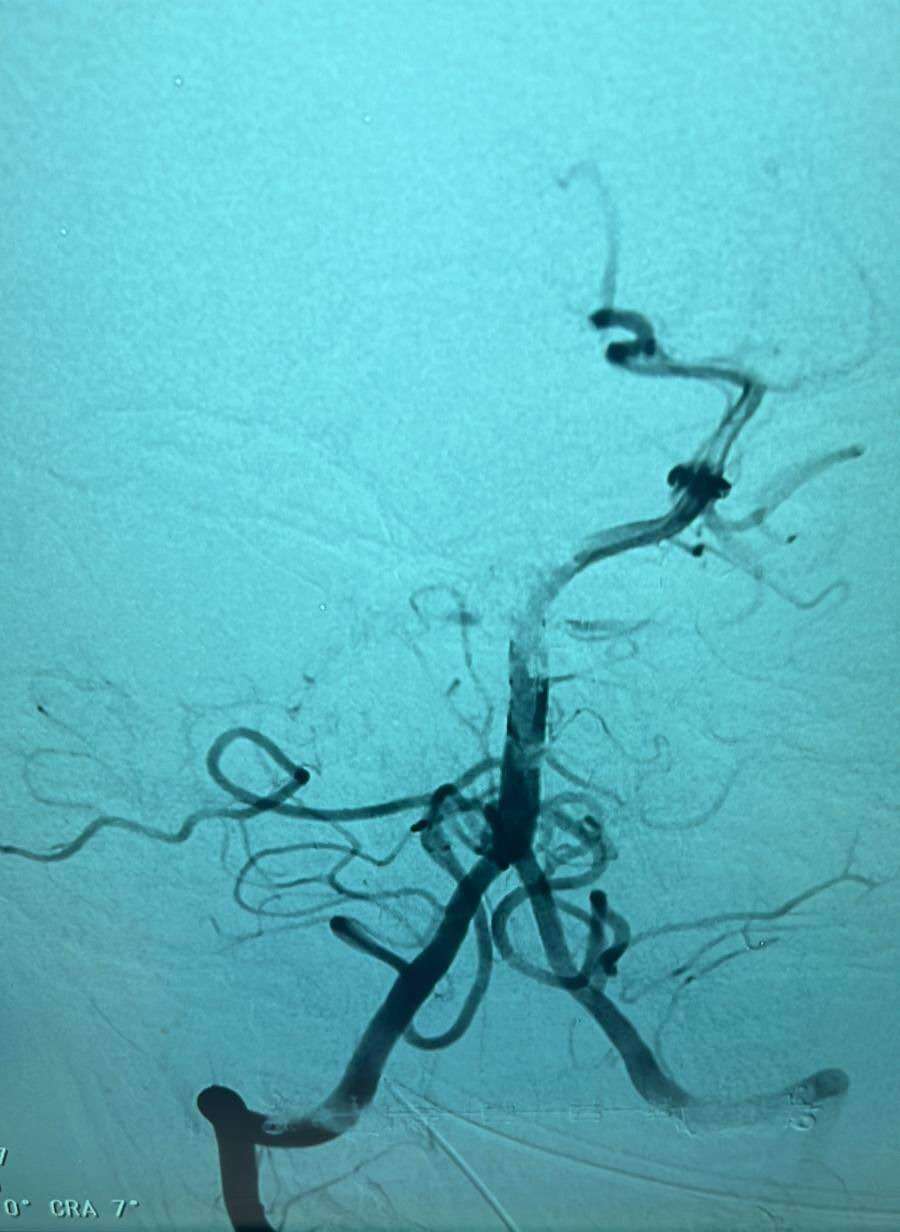

עם הגעתו בתחילה למרכז רפואי העמק, הסמוך למקום מגוריו, בוצעה לו בדיקת CT אנגיוגרפיה, בה התגלה כי הוא סובל מקריש דם החוסם את העורק הבזילארי (עורק גדול וחשוב במוח), מה שגרם לו לשבץ מוחי. הנער, שטופל תחילה במיון ילדים של מרכז רפואי העמק, קיבל טיפול תרופתי והועבר בדחיפות לצינתור מוח לביה”ח בנהריה, שבוצע על ידי מנהל היחידה, ד”ר שאדי ג’השאן.

במהלך צינתור המוח, שהיה מורכב ביותר, נשלף באופן מלא קריש הדם, שחסם את העורק במוח, ובסיום הועבר הנער לאישפוז ביחידה לטיפול נמרץ ילדים, להמשך התאוששות. לאחר שהתעורר וחזר להכרה מלאה, הועבר הנער למחלקת ילדים, כדי לבדוק מה גרם למצב זה.

ד”ר ג’השאן: “מאז הקמת היחידה לצינתורי מוח בשנת 2014, לא זכור לי מקרה, בו נער בגיל כה צעיר נאלץ לעבור צינתור מוח, בגין חסימה בעורק המוח. הוא הגיע ממש בדקה ה-90. הצינתור היה מורכב ומאתגר ביותר, מכיוון שקריש הדם היה גדול מאוד ומוקם באזור מורכב ורגיש במיוחד במוח”.